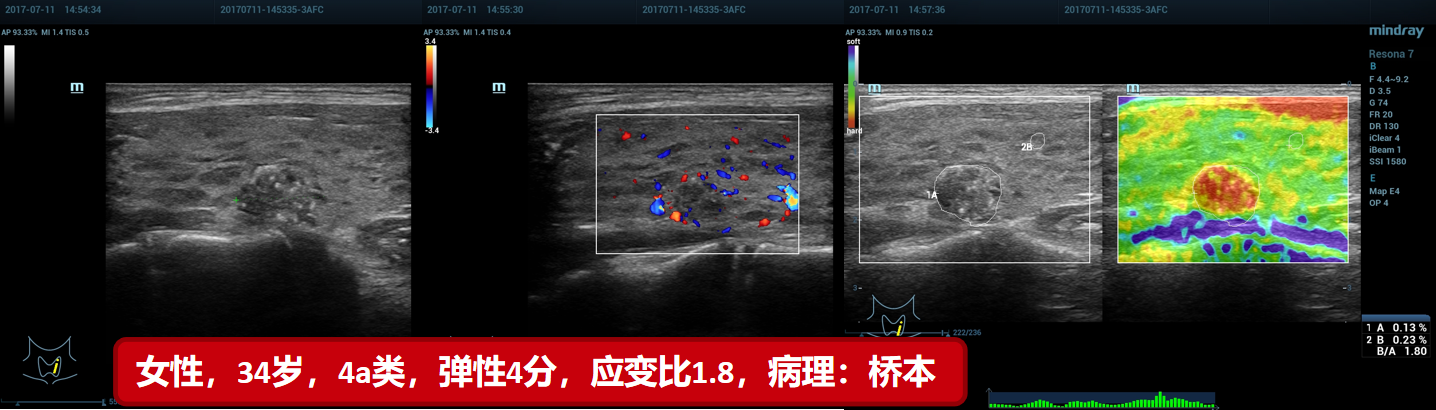

7、桥本(贵州医科大附属医院)

7、桥本(贵州医科大附属医院)